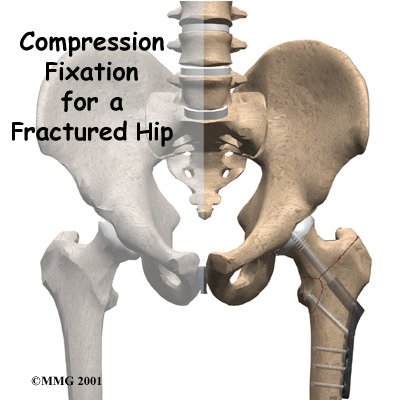

A fractured hip can be a life-threatening problem. The hip fracture itself isn't usually a difficult problem to treat with surgery. But once the fracture occurs, it brings with it all the potential medical complications that can arise when aging adults are confined to bed. The goal of treatment is to get patients moving as quickly as possible after surgery. Fixing the fracture with a compression hip screw and metal plate is fairly simple and usually allows patients to get up and start moving shortly after surgery.

Fixing the hip fracture surgically with a special type of metal plate and screw, called a compression screw, does two things. First, it helps align the bone fragments and hold them in the proper position. Second, the fixation device is strong enough to keep the bones in place as you begin to move about. Before these devices were used, a patient needed to remain in bed usually with traction to hold the bones in alignment. The fixation now holds the bones in place while the bone heals. This allows you to get out of bed sooner because the metal plate and screw are strong enough to hold the bone fragments in place as you move.

Next, the surgeon makes an incision over the side of the thigh. A large metal screw is placed through the side of the hip into the femoral head. With the help of the fluoroscope, the surgeon attaches a metal plate to the side of the femur with four to eight small metal screws. The procedure can usually be finished in less than an hour depending on how many fragments of bone are involved in the fracture.